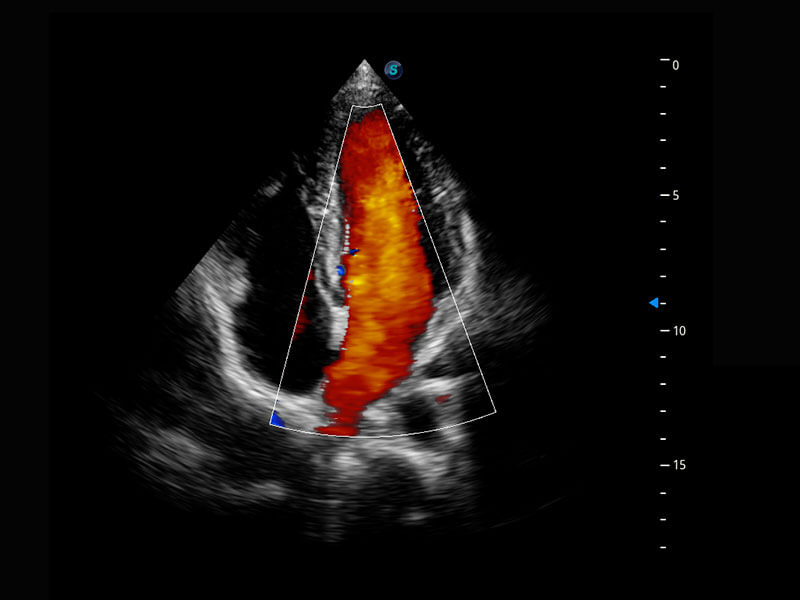

P60搭載一系列胎兒心臟成像技術(shù),實(shí)現(xiàn)精細(xì)的胎兒心臟評(píng)估。

四腔心血流